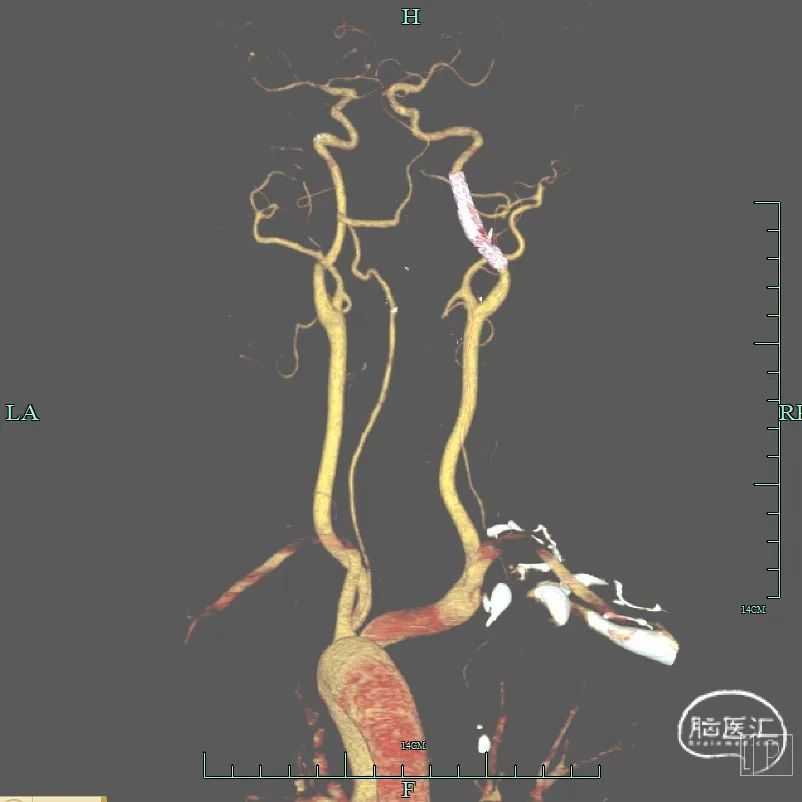

入院查体:神清,言语清晰,对答基本切题,双侧瞳孔等大圆形,对光反射灵敏,眼球向左、向上、向下运动不能,左侧鼻唇沟稍浅,口角右歪,伸舌左歪,左上肢肌力2-级,左下肢肌力3+级,右侧肢体肌力5级,双侧巴氏征阳性。NIHSS评分7分。头颅MRA:右侧颈内动脉闭塞。

为进一步评估梗死大小和颅内情况,磁共振显示颈内动脉闭塞,小的核心梗死。

术后三个月随访:mRS 0分,颈部血管CTA显示支架形态良好。